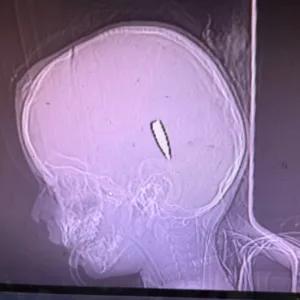

وقالت نيوريورك تايمز في بيانها :”جمع تحقيق استقصائي حديث شهادات مباشرة من 65 من المتخصصين في مجال الصحة المقيمين في الولايات المتحدة والذين عملوا في غزة على مدار العام الماضي، والذين شاركوا بأكثر من 160 صورة وفيديو مع قسم الرأي في صحيفة تايمز لتأكيد رواياتهم التفصيلية عن الأطفال في سن ما قبل المراهقة الذين أصيبوا برصاصة في الرأس أو الصدر. وبعد النشر، شكك بعض القراء في دقة الروايات ومصداقية ثلاث صور مقطعية معروضة. وهذه الانتقادات لا أساس لها من الصحة”.

وقالت الصحيفة :”قمنا بتحرير هذا المقال بعناية شديدة قبل نشره، والتحقق من صحة الروايات والصور من خلال الأدلة الفوتوغرافية والفيديو الداعمة وبيانات الملفات التعريفية. كما قمنا بفحص أوراق اعتماد الأطباء والممرضات، بما في ذلك أنهم سافروا إلى غزة وعملوا فيها كما زعموا. وعندما ظهرت أسئلة حول صدق الصور المدرجة في المقال، قمنا بعمل إضافي لمراجعة النتائج السابقة التي توصلنا إليها. لقد قدمنا الصور الممسوحة ضوئيًا إلى جولة جديدة من الخبراء المتعددين المستقلين في جروح الطلقات النارية والأشعة والصدمات لدى الأطفال، والذين شهدوا على مصداقية الصور وقارنا الصور بمقاطع فيديو من فحوصات الأشعة المقطعية المقابلة لها بالإضافة إلى صور جروح الأطفال الصغار”.

وأضاف البيان:”ورغم أن محررينا لديهم صور لتأكيد صور الأشعة المقطعية، إلا أننا قررنا بسبب طبيعتها الصادمة أن هذه الصور ـ التي تصور أطفالا مصابين بطلقات نارية في الرأس أو الرقبة مروعة للغاية بحيث لا يجوز نشرها واتخذنا قراراً مماثلاً فيما يتصل بأكثر من أربعين صورة وفيديو قدمها الأطباء والممرضات الذين شملتهم الدراسة، والتي تصور أطفالاً صغاراً مصابين بطلقات نارية مماثلة”.